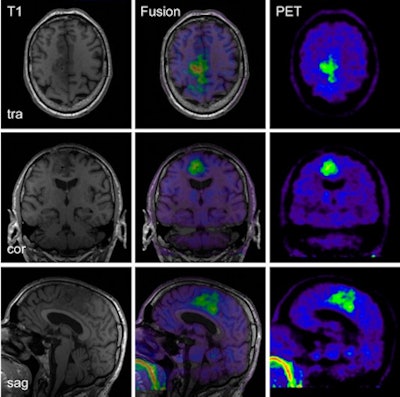

![]() |

| PET/MR images of a 60-year-old patient with anaplastic astrocytoma with right parafalxial tumor extension. MRI and PET datasets were simultaneously acquired at coronal (cor), sagittal (sag), and transverse (tra) sections. Images courtesy of the Journal of Nuclear Medicine. |

The one exception was when a 4-mm Gaussian filter was not used and the PET datasets from concurrent PET/MRI scans "exhibited slight streak artifacts, which were best visible in the sagittal and coronal reformations," the researchers noted. "After filtering, these artifacts were hardly visible."